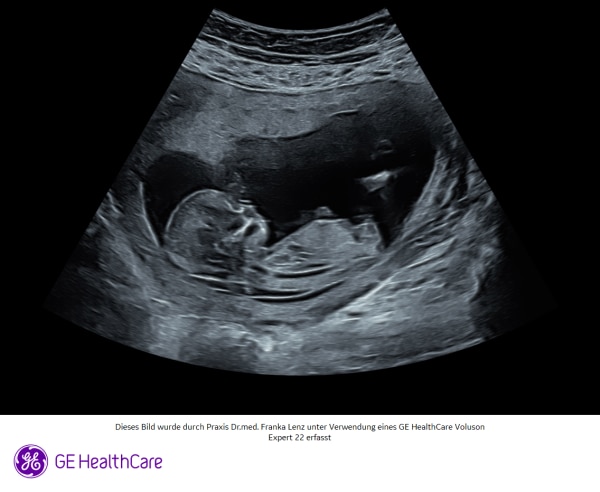

Hallo Ihr Lieben🥰 Ich bin aktuell in der 14. Schwangerschaftswoche mit unseren dritten Wunder zu kleinen Info. Ich bin 29 Jahre alt. Ich hatte den Double Test Machen lassen Als ich dann beim letzten Mal bei der Feindiagnostik war, wurde eine Nackenfalte von 2,4 gemessen. Mit dem Blutwerten zusammen wurde ein Trisomie Risiko von 1:131 Diagnostiziert. Ich bin ehrlich gesagt fix und fertig und weine jeden Abend. Ich habe dann einen NIPT Test machen lassen. Das Ergebnis kriegen wir aber erst Mittwoch. Kennt sich jemand mit den Werten von den Double Test aus? Ich finde leider nichts da drüber ich weiß vielleicht sollte ich mich nicht zu sehr aufregen und darüber nachdenken. Aber vielleicht kann der ein oder andere mich verstehen, dass ich mir gerade sehr viel Sorgen mache. Schon mal vielen Dank, dass ihr meinen Beitrag gelesen habt. Ich wünsche euch eine wunderschöne Kugel Zeit.❤️

Bild zu Risiko Tresomie 21 - Forum für Mai - Mamis